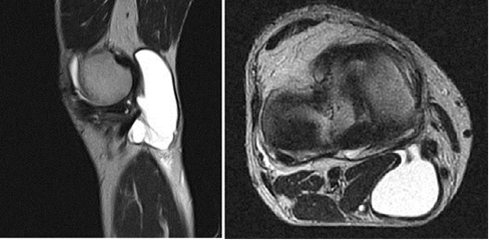

De los estudios imaginológicos la IRM ofrece los mejores resultados, permite detectar la válvula entre el QB y la articulación, por lo general entre la cabeza medial del gastrocnemio y el tendón del semimembranoso, esta estructura es observada con mayor claridad en la vista axial (Fig.1). 20,21,22